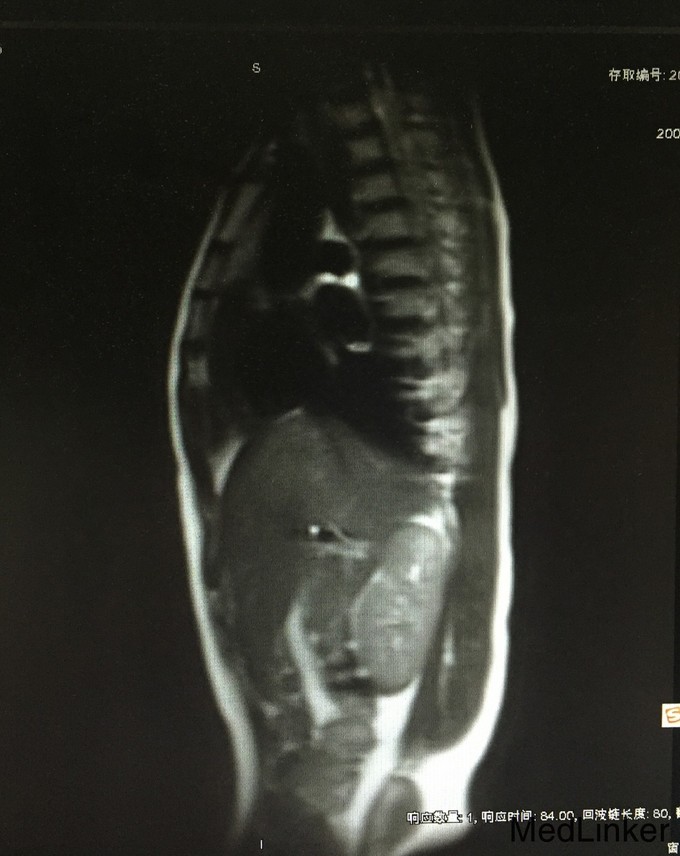

查体:生命体征平稳;双侧乳腺发育稍差。妇检:外阴呈女性生殖特征,阴蒂肥大,可见尿道开口;阴道外口可见,无性生活史,未内诊。肛查示子宫小,盆腔右侧可及包块。 辅查:2015-08-15妇科B超示:子宫小,左侧卵巢内未见明显卵泡结构;右侧附件区囊性肿块,待排畸胎瘤(43mm*30mm)。 2015-08-24查染色体示46XY,t(4;20)(q27;p13)。 2015-09-28我院查盆腔MR示双侧附件肿块,性质待定,考虑卵巢来源;阴茎发育短小,子宫小,符合双性畸形改变。

诊断:两性畸形 治疗:请我院资深超声科主任医师复查妇科B超示双侧两性母细胞瘤可能。查腹部MR:1.右侧附件区囊实性肿块,左侧附件区实性肿块,性质待定,考虑卵巢来源肿瘤。 2.阴茎发育短小,子宫稍小,符合双性畸形改变。 3.双侧肾脏及输尿管、膀胱MRI扫描未见异常。 4.上腹部MRI扫描未见异常。 请儿科教授会诊,46XY性发育障碍,意见:女性表型含Y染色体者发生性腺恶性肿瘤可能性大,建议腹腔镜性腺切除。查皮质醇8AM正常及ACTH 8AM,均正常。行腹腔镜下双侧性腺肿瘤切除术+双输卵管切除术。术中冰冻结果:良性。